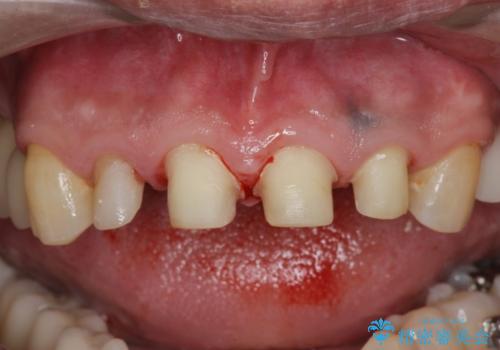

「 放置した虫歯 」 前歯セラミック治療

- 前歯の虫歯に気付きながらも放置し、一念発起し治療を希望され来院されました。

虫歯のマイクロスコープによる丁寧な除去、根管治療、深い虫歯に対する挺出(エクストリュージョン)および歯周外科を行ったのち精度の高いセラミッククラウン製作治療を計画します。

虫歯の放置により、根管治療や深い虫歯に対する処置が必要になりましたが丁寧に一つづつ処置を行ったことで抜歯をすることなく歯を残すことができました。

セラミッククラウンの製作をする前に、歯内・歯周環境の整備は非常に大切です。